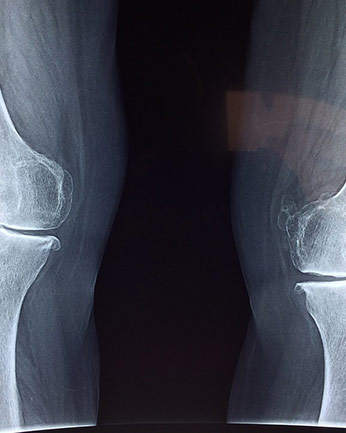

Učenici mogu upoznati građu kosti radom u skupini. Svaka skupina neka promotri uzdužno prerezanu kost (svinjska/goveđa) lupom. Na prirodnome materijalu neka pronađu pokosnicu, čvrsto koštano tkivo, spužvasto tkivo, koštanu srž i hrskavicu i usporede s crtežom i tekstom Građa kosti koji ste postavili u digitalnoj bilježnici OneNote. U digitalnoj bilježnici postavite konceptualnu tablicu u koju će učenici upisati (npr. dio kosti, gdje se nalazi i koja mu je uloga) na posebnu stranicu za svaku skupinu te nacrtati kost i imenovati njezine dijelove. Konceptualna tablica može vodoravno sadržavati dijelove kosti, a okomito gdje se nalazi i koja mu je uloga.